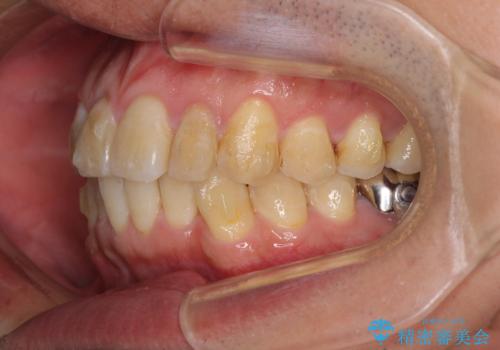

前歯のデコボコと下顎の八重歯 インビザラインによる矯正治療

- 前歯のデコボコや八重歯を気にして来院された患者様です。

インビザラインを用いて、歯列を整えることとしました。

下顎前歯は後戻りを起こしやすいため、舌側を細いワイヤーで固定し、マウスピース型リテーナーで保定を行うこととしました。